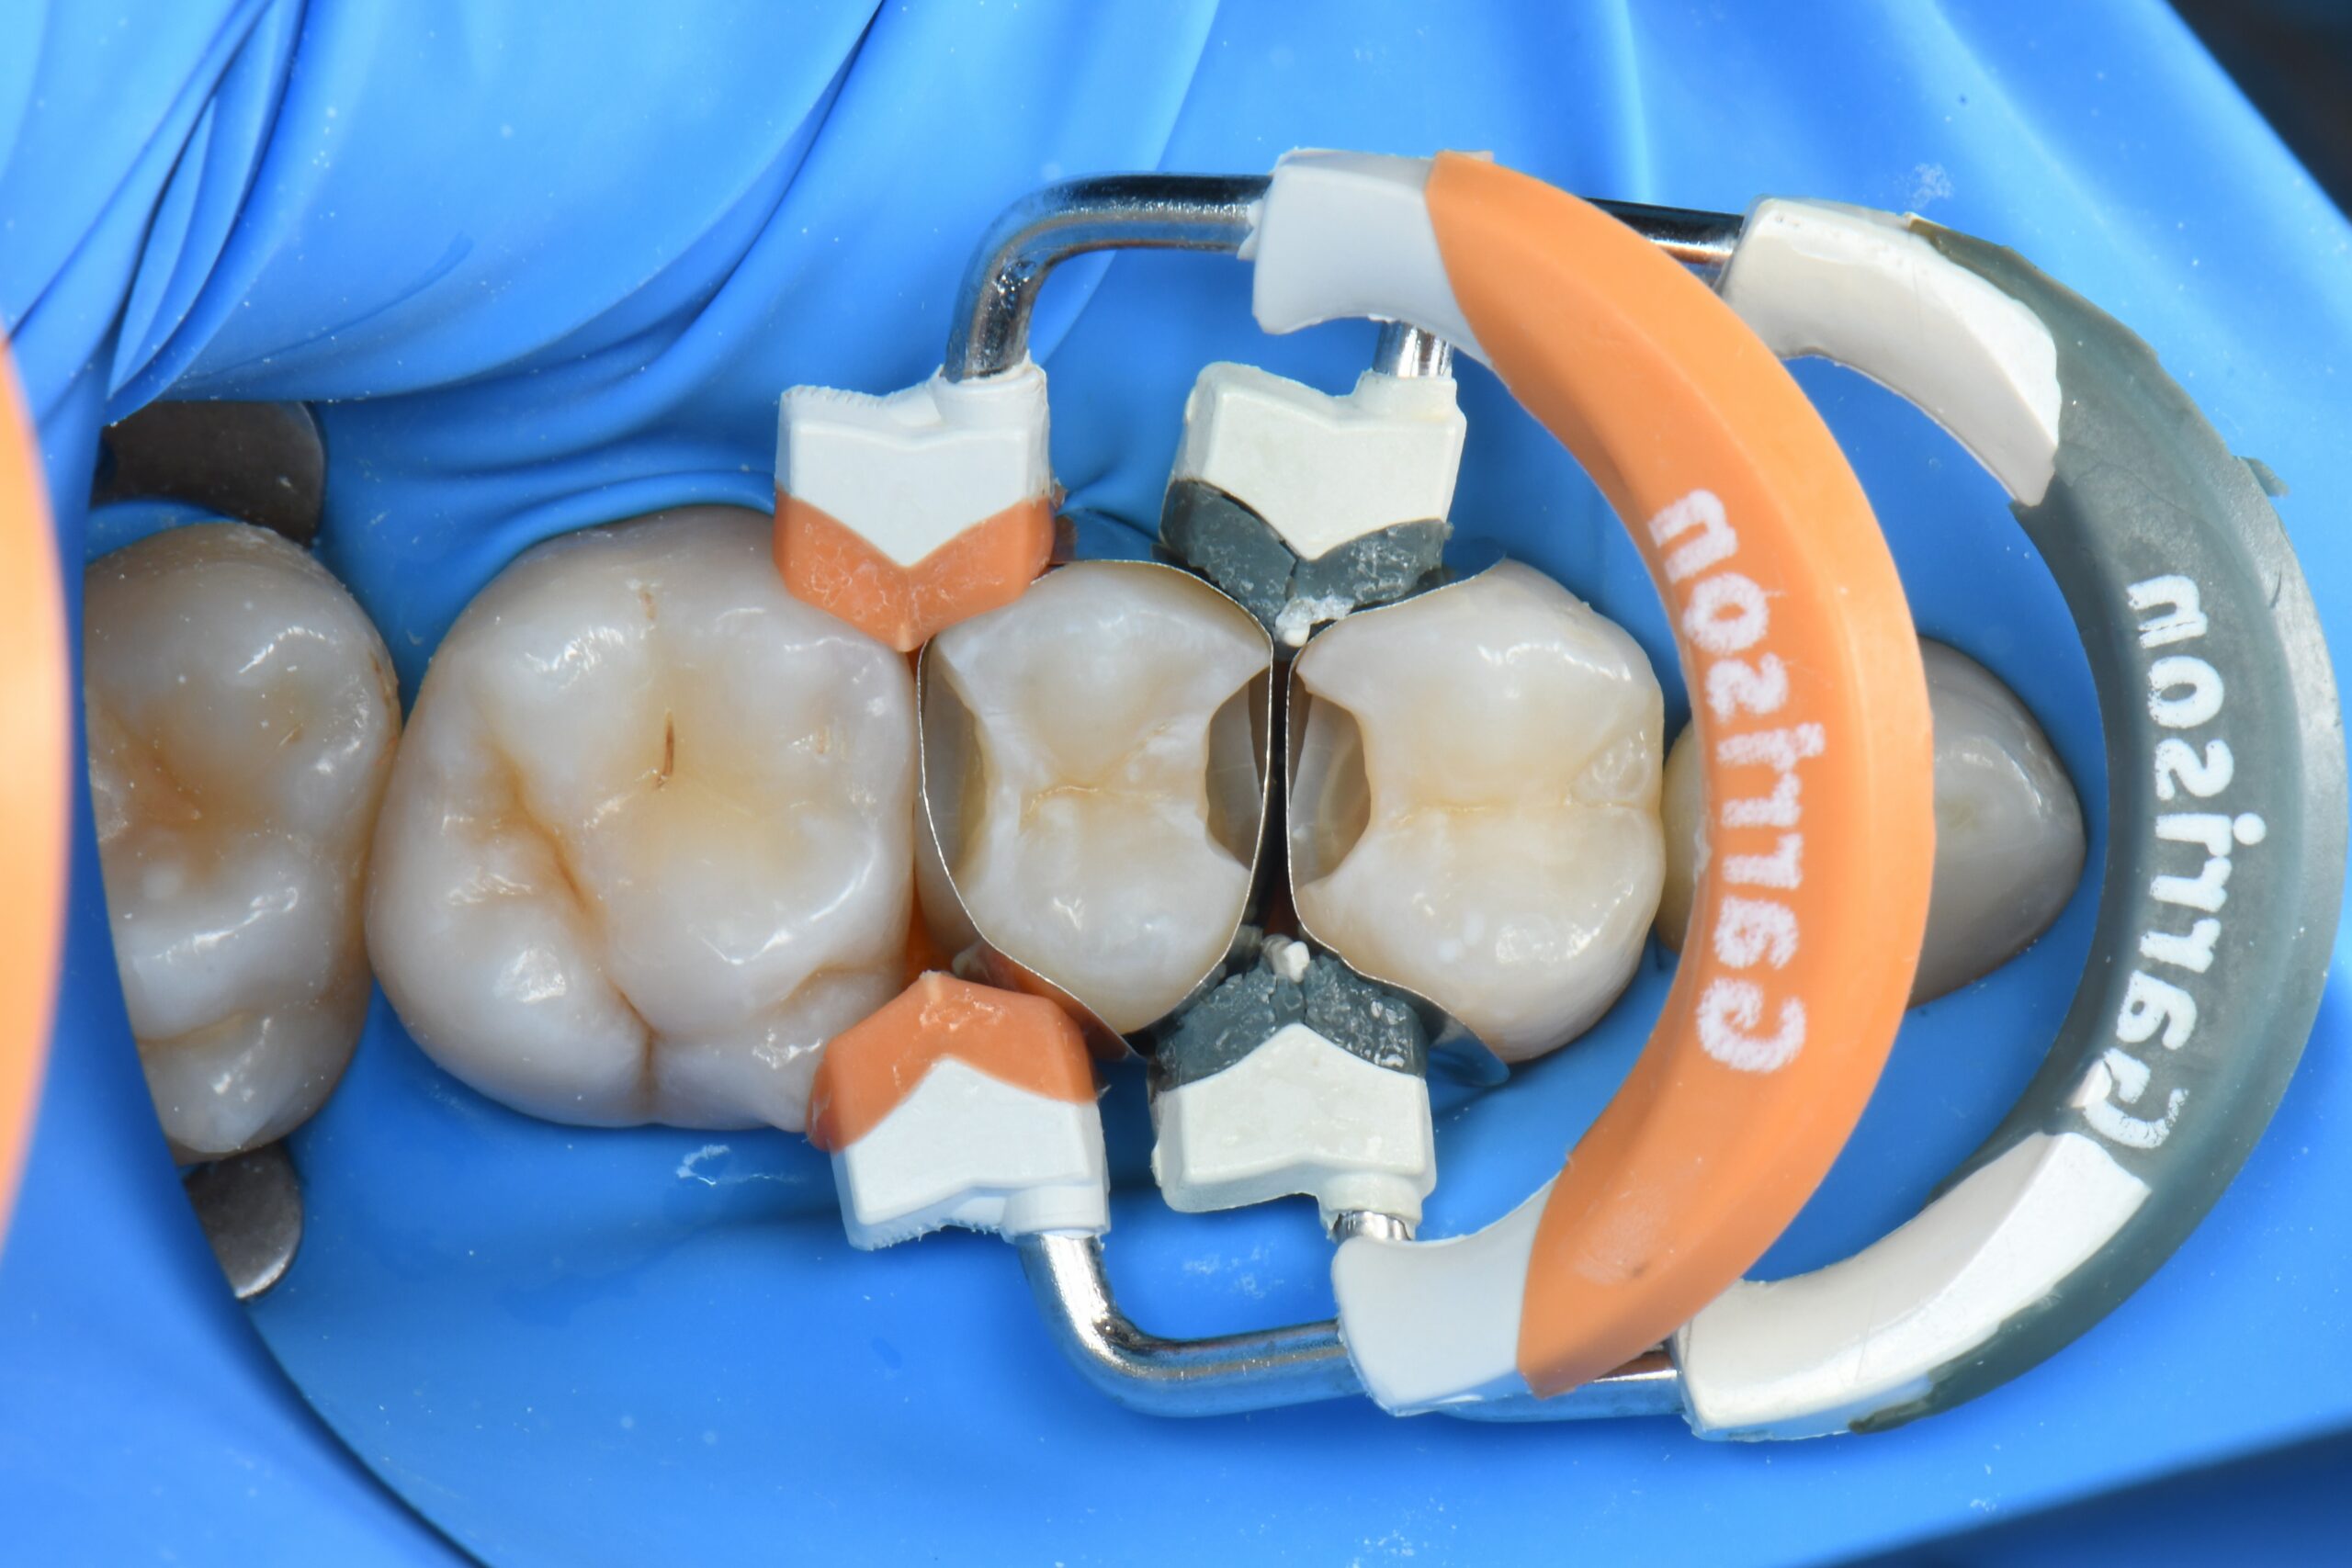

Close-up of molar teeth with dental matrix bands and wedges in place for restorative treatment

Sectional matrices, wedges and rings are properly placed, and selective enamel etching is performed.